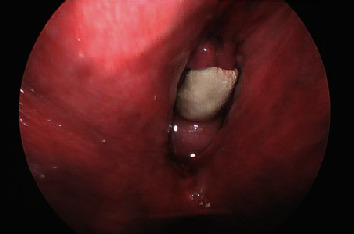

阴道结石是一种罕见的临床症状,可能在阴道尿液淤积的情况下出现。导致结石形成的因素有很多,结石的大小、位置和邻近结构的位置都会使处理变得复杂。一般来说,一旦确诊为阴道结石,应立即将其取出,并彻底评估周围的解剖结构,看是否有继发性瘘管、侵蚀或异物存在。本报告介绍了一例患有出血性膀胱炎的老年患者,其阴道结石形成于暴露的尿道中段吊带网片上。本报告强调了病理生理学、诊断因素和治疗方法。

The presence of a vaginal calculus is a rare clinical entity which may develop in the setting of vaginal urinary stagnation. Numerous factors contribute to stone formation, and management can be complicated by variations in size, location of the stone, and location of adjacent structures. Generally, once diagnosed, vaginal calculi should be removed and surrounding anatomy should be evaluated thoroughly for secondary fistula, erosion, or presence of an instituting foreign body. This report presents a case of vaginal calculus formation on exposed midurethral sling mesh in an elderly patient with hemorrhagic cystitis. This report emphasizes contributing pathophysiology, diagnostic factors, and treatment.